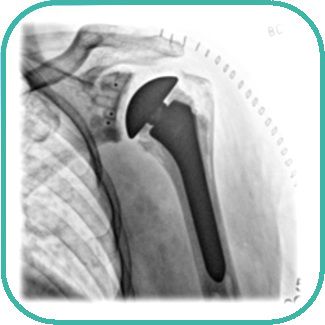

Wann ist ein Gelenksersatz an der Schulter notwendig?

Die Schulter kann in ihrer Funktion und Beweglichkeit schmerzhaft beeintrachtigt werden durch

- Verschleißerscheinungen

- Erkrankungen oder

- Verletzungen

Sind die Gleitflächen des Schultergelenks dadurch dermaßen geschädigt oder zerstört, dass weder konservative Therapien noch gelenkerhaltende Operationen Abhilfe versprechen, wird die Implantation einer Schulterprothese notwendig.

Auf diese Weise sollen die Schmerzen in der betroffenen Schulter langfristig beseitigt und die maximale Beweglichkeit des Schultergelenks wiederhergestellt werden.

Welche Operationen gibt es in der Schulterprothetik?

- Oberflächenersatz (kleine Schulterprothese)

- Teilersatz: Hemiprothese (Oberarmkopfprothese)

- Komplettersatz / Schulter-TEP (Totalendoprothese) - anatomische Schulterprothese

- Komplettersatz / Schulter-TEP (Totalendoprothese) - inverse Schulterprothese (umgekehrte Anordnung von Gelenkkopf und -pfanne, bei verkümmerten Schulterblattmuskeln)

- Wechseloperationen für Schulterprothesen

Wie wird ein Schultergelenk implantiert?

Je nachdem, ob es sich um eine Teilprothese der Schulter oder eine Schultertotalendoprothese (Schulter-TEP) handelt, besteht das Implantat aus ein bis drei Komponenten:

- Oberarmkopfkompomente

- Prothesenschaft

- künstliche Schulterpfanne (Glenoidersatz)

Die Verankerung im Knochen erfolgt je nach Komponente und individuellen Gegebenheiten

- zementfrei mit Presssitz

- zementiert

- mit Schrauben